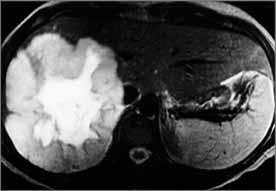

Ogniskowy rozrost guzkowy (FNH – focal nodular hyperplasia)

Epidemiologia:

Obraz kliniczny: Rozpoznanie: